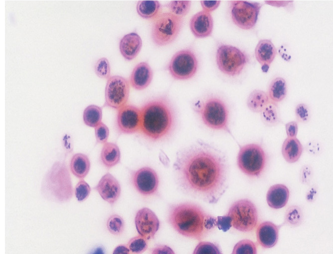

top: hematoidin bilirubin

Bottom: erythropagocytosis